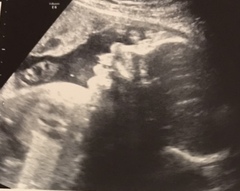

Had my second growth scan today, baby’s doing fine he’s measuring correctly in terms of weeks. He even had his hand to his head as if to say ‘dear god Mum how many times do we have to come here’ lol

Gem173 · 03/07/2018 16:53

Here’s another photo of little one :) also bought the baby a nemo swim costume 😂 he’s going swimming once he’s 8 weeks to start learning. Oh Mum insists he goes. He’s gunna look so daft!